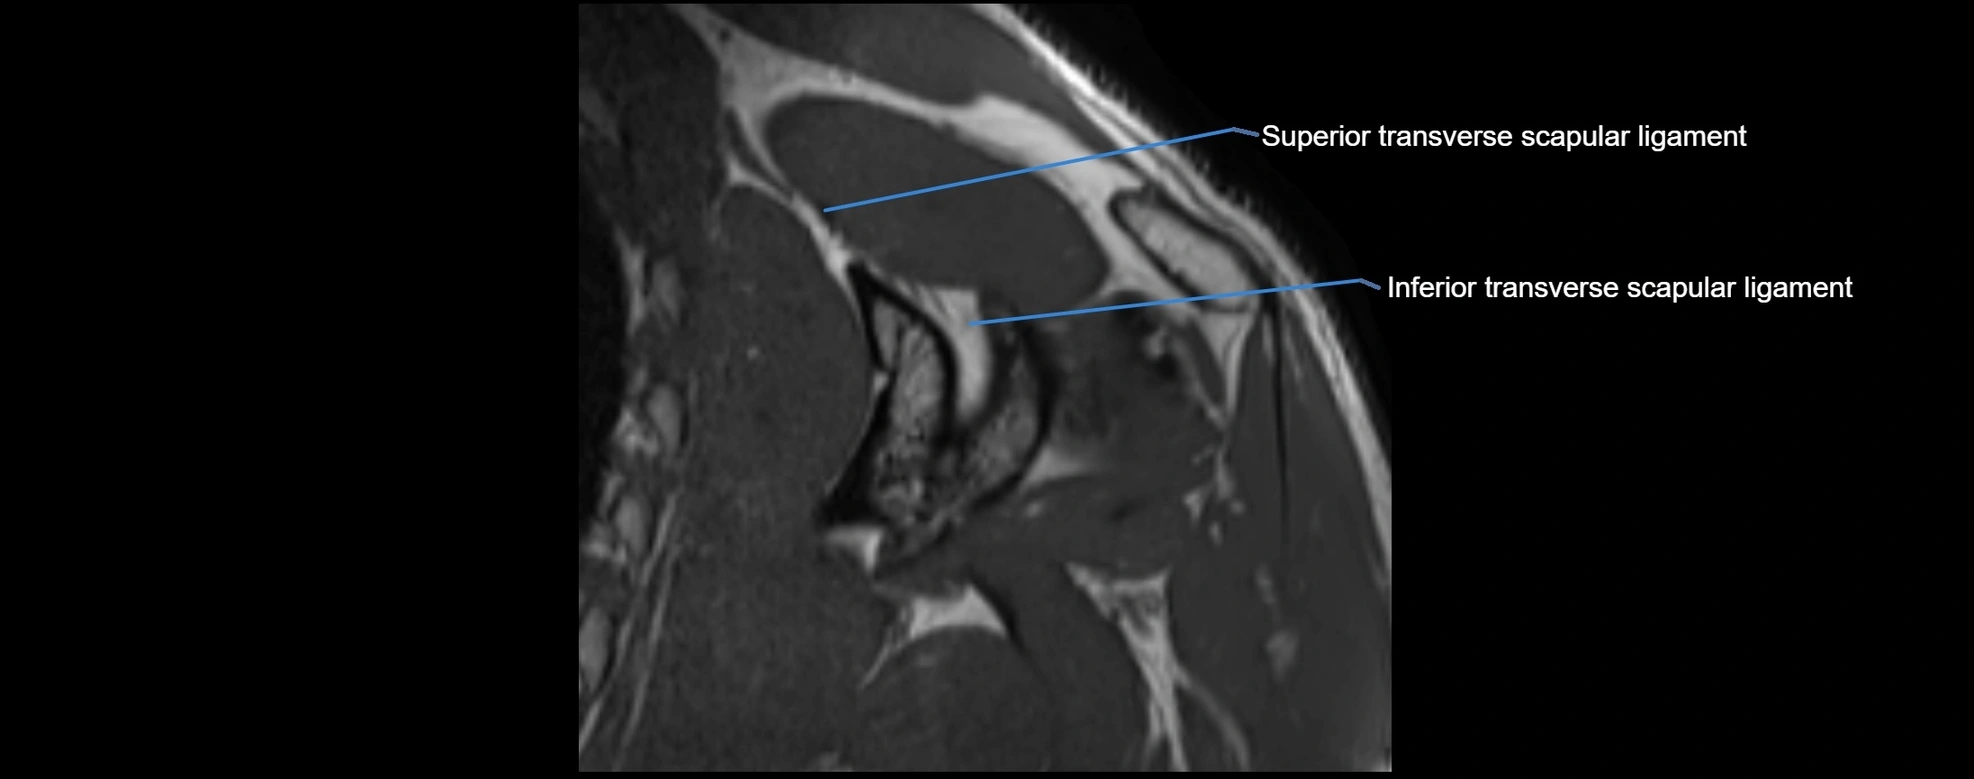

MRI images

image

CT image